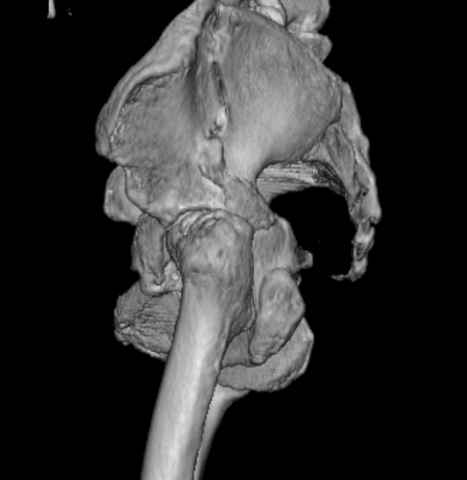

Уважаемые коллеги, возник вопрос по лечению нашей пациентки 60 лет. Около года назад множественная травма: в том числе Т-образный перелом вертлужной впадины. На сегодняшний день сращение отломков имеется на ограниченных участках, имеется дефект задней колонны вертлужной впадины. Движения неплохие, ходит с костылями, приступая на ногу. По мнению эдопротезистов при установке антипротрузионного кольца или октопуса не хватит костного материала и необходимо перед протезированием выполнить реконструкцию впадины, иначе чашка протеза неминуемо выпадет.Просьбы поделиться положительным и отрицательным опытом протезирования в подобных случаях.Возможно ли обойтись без реконструкции?Или лучше с ней?С уважением РАВ.

По моему мнению предварительну реконструкцию делать нет необходимости. Операцию надо выполнять одномоментно с пластикой вертлужной впадины. по поводу того, что не хватит головки. Да не исключено. Но ведь есть и другие материалы. Лучше при таком раскладе иметь в запасе замороженную головку. если нет возможности, как вариант два крыла подвздоной кости + хронос или его аналоги. По поводу выбора конструкции. Октопус в данной ситуации будет совсем не уместен, т.к. имеется дефект задней колонны вертлужной впадины. Да как конструкция октопус встанет не плохо. Но в функциональном плане не будет хорошей задне латерально и заднемедиальной точек опры впадины на период перестройки трансплатов. И по этому в данной ситуации более уместно кольцо Бурх(г)-Шнайдера с аналогичной пластикой, но возможнотью зафиксировать отломки задней колонны, крыши. Естественно цементная чашка с козырьком из кросс линк полиэтилена. Гололвка керамика, ножка бесцементная можно Цваймюллера или любой другой конструкции, они сейчас все хороши.

Основное внимание необходимо уделить стабильности костных фрагментов в зоне перелома вертлужной впадины. Если имеется нестабильность я предпочел бы Октопус для остеосинтеза и стабильности вертлужной впадины. Этот момент является основным для успешного протезирования.